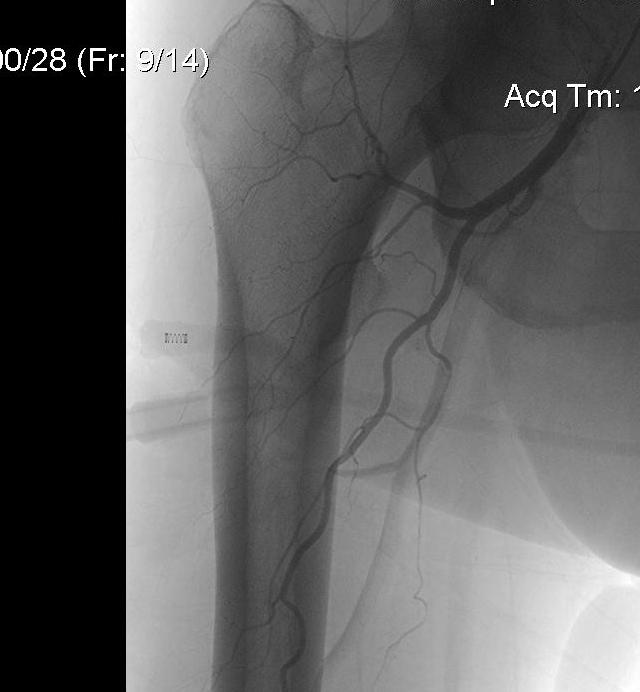

Profunda femoris

Artery to thigh muscles

- exits laterally at termination of femoral sheath

- 3-4 cm distal to inguinal ligament

- arises from lateral side

- passes between pectineus and adductor longus

- runs behind adductor longus

- runs down on adductor brevis and magnus

- gives 4 perforating branches